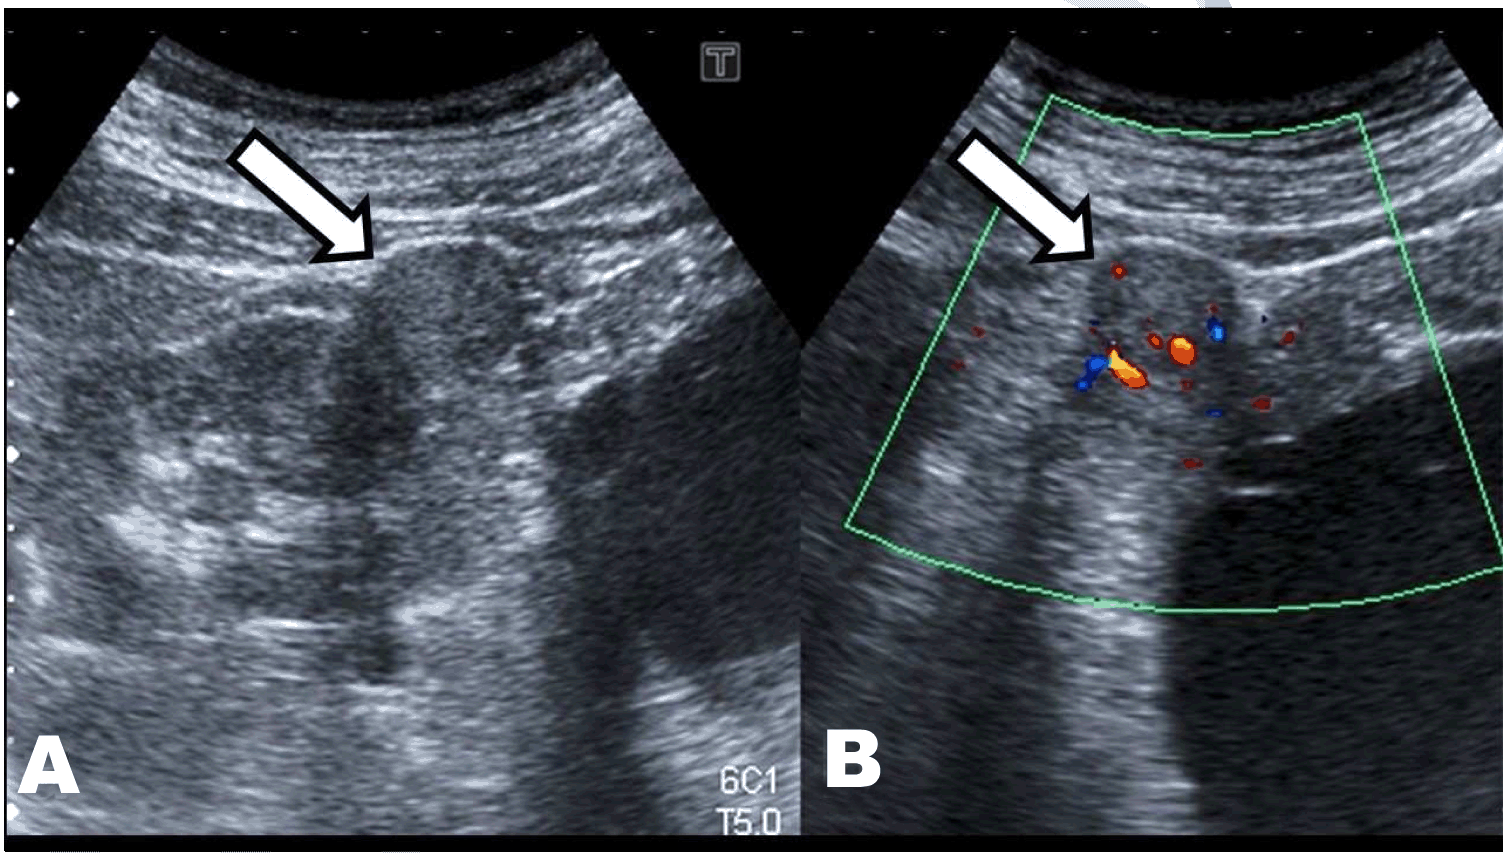

On February 2013, a 76-year-old male was sent to our nephrology unit to evaluate renal disease. He was asymptomatic and had been diagnosed with hypertension, overweight, benign prostatic hypertrophy and chronic obstructive pulmonary disease several years ago. His one daughter was also diagnosed with a renal cyst. His serum creatinine was 1.6 mg/dL, eGFR 42 mL/min, albumin/creatinine ratio in spot urine sample 2.8 mg/g and normal urinary sediment. Ultrasonography showed a slight enlargement of both kidneys and the presence of multiple bilateral cysts, predominantly with cortical distribution, classified as Bosniak I. No complex cysts that required monitoring or solid lesions were found (Figure 1). Therefore, he was diagnosed with Autosomal Dominant Polycystic Kidney Disease (ADPKD) and follow-up was drawn. He was successfully treated with losartan 50 mg/day. On July 2014, a new ultrasound control revealed the appearance of an echogenic nodule on the upper pole of the right kidney with vascularization in Doppler mode (Figure 2). The study was completed by computed tomography scan that confirmed the presence of a solid nodule of 23 mm on the right kidney with early contrast enhancement after i.v. iodine contrast administration. These findings strongly suggested the existence of superimposed renal cell carcinoma (RCC) (Figure 3). Considering his age and co-morbidities conservative treatment was planned.

Figure 2: Ultrasound image of the upper pole of right kidney. (A) B-mode image with an echogenic nodule, with rounded morphology (white arrow), (B) Doppler mode reveals the presence of vascularization in this nodule (white arrow).